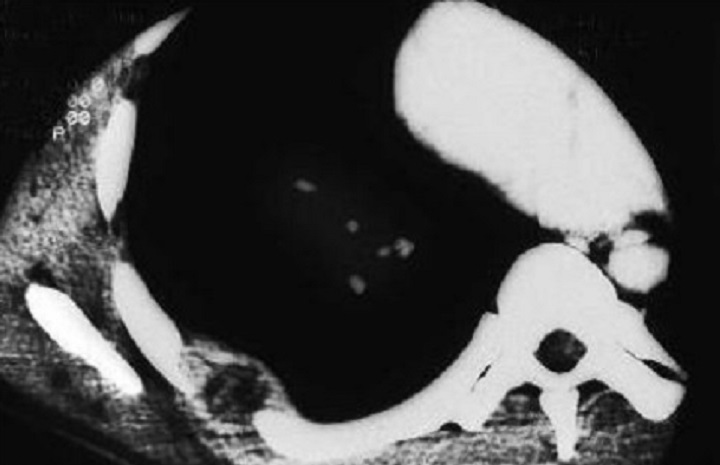

Aspect d'élargissement et

épaississement du cartilage au niveau de articulation

sternocostale gauche et oedème de la moelle

osseuse dans sous-chondral . Image radiologique TDM

coupe axial d'une syndrome Tierzt gauche du thorax

Même cas en coupe TDM coronal

( frontal ) avec image de

oedème de la moelle

osseuse dans sous-chondral gauche et élargissement et

épaississement du cartilage de articulation manubrium -costale

gauche etr en vue très nette |